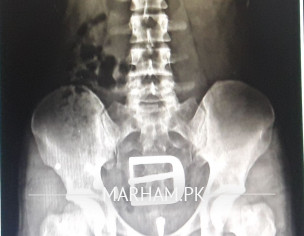

Asking For Self, Male 23, Mandi baha uddin

i have psoriatic spondylitis since last six my back becomes stiff especially in the morning & i can't move freely.i have psoriasis should I do? how i can get rid of this sharp pain and stiffness please please guide me.i have consulted many doctors.i m attaching my x ray.

where is lateral view start tab BACKIN 50 ng half Tds